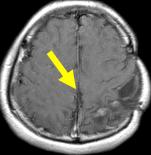

病患A小弟, 在3歲時突然產生腦中風出血, 造成右側肢體無力, 經診斷為腦動靜脈畸形,在14歲時, 於本院接受加馬刀放射手術治療, 經4年後, 血管瘤消失, 成效良好, 目前A小弟已高中, 每天可騎腳踏車上

文字方塊: 每年磁共振造影追蹤動靜脈畸形可見逐年消失

文字方塊: 2007.02.26

文字方塊: 病患A 14歲 男性

診斷:動靜脈畸形